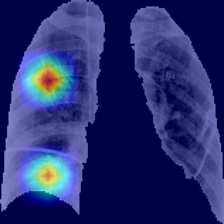

The areas of significant interest used by the CNN for discrimination purposes are identified using a qualitative analysis based on a Gradient-weighted Class Activation Mapping (Grad-CAM) [38]. This is an explainability method that serves to provide insights about the manners on how deep neural networks learn, pointing to the most significant areas of interest for decision-making purposes. The method uses the gradients of any target class to flow until the final convolutional layer, and to produce a coarse localization map which highlights the most important regions in the image identifying the class. The result of this method is a heat map like those presented in Fig. 1, in which the colour encodes the importance of each pixel in differentiating among classes.

The regions of interest identified by the network, were analyzed qualitatively using Grad-CAM activation maps [38]. Results shown by the activation maps, permit the identification of the most significant areas in the image, highlighting the zones of interest that the network is using to discriminate. In this regard, Fig. 1, presents examples of the Grad-CAM of a control, a pneumonia, and a COVID-19 patient, for each of the three experiments considered in the paper. It is important to note that the activation maps are providing overall information about the behaviour of the network, pointing to the most significant areas of interest, but the whole image is supposed to be contributing to the classification process to a certain extent.

The second row in Fig. 1 shows several prototipical results applying the Grad-CAM techniques to experiment 1. The examples show the areas of significant interest for a control, pneumonia and COVID-19 patient. The results suggest that the detection of pneumonia or COVID-19 is often carried out based on information that is outside the expected area of interest, i.e. the lung area. In the examples provided, the network focuses on the corners of the XR image or in areas around the diaphragm. In part, this is likely due to the metadata which is frequently stamped on the corners of the XR images. The Grad-CAM plots corresponding to the experiment 2 (third row of Fig 1), indicates that the model still points towards areas which are different to the lungs, but to a lesser extent. Finally, the Grad-CAM of experiment 3 (fourth row of Fig 1) presents the areas of interest where the segmentation procedure is carried out. In this case, the network is forced to look at the lungs, and therefore this scenario is supposed to be more realistic and more prone to generalizing as artifacts that might bias the results are somehow discarded.

We stand on the fact that automatic diagnosis is much more than a classification exercise, meaning that many factors have to be had in mind to bring these techniques to the clinical practice. To this respect, there is a classic assumption in the literature that the associated heat maps –calculated with techniques such as Grad-CAM– provide a clinical interpretation of the results, which is unclear in practice. In light of the results shown in the heat maps depicted in Fig. 1, we show that experiment 1 must be carefully interpreted. Despite the high-performance metrics obtained in experiment 1, the significant areas identified by the network are pointing towards certain areas with no clear interest for the diagnosis, such as corners of the images, the sternum, clavicles, etc. From a clinical point of view, this is clearly biasing the results. It means that other approaches are necessary to force the network to focus on the lungs area. To this respect, we have developed and compared the results with two preprocessing approaches based on cropping the images and segmenting the lungs area (experiment 2 and experiment 3). Again, given the heat maps corresponding to experiment 2, we also see similar explainability problems to those enumerated for experiment 1. Reducing the area of interest to that proposed in experiment 2 significantly decreases the performance of the system due to the removal of the metadata that usually appear in the top left and/or right corner, and to the removal of areas which are of interest to categorize the images but have no interest from the diagnosis point of view. However, while comparing experiment 2 and 3, performance results improve in the third approach, which focuses on the same region of interest but with a mask that forces the network to see only the lungs. Thus, results obtained in experiments 2 and 3 suggest that eliminating the needless features extracted from the background or non-related regions improves the results. Besides, the third approach (experiment 3), provides more explainable and interpretative results, with the network focusing its attention only in the area of interest for the disease. The gain in explainability of the last method is still at the cost of a lower accuracy with respect to experiment 1, but the improvement in explainability and interpretability are considered critical to translate these techniques to the clinical setting. Despite the decrease in performance, the proposed method in experiment 3 has provided promising results, with an Acc of , BAcc of , GMR of and AUC of .

The COVID-Net has also demonstrated being a good starting point for the characterization of the disease. Indeed, the outcomes of the paper suggest the possibility to automatically identifying the lung lesions associated with a COVID-19 infection (see Fig.1) by analyzing the Grad-CAM mappings of experiment 3, providing an explainable justification about the way the network works. However, the interpretation of the heat maps obtained for the control class must be carried out carefully. Whereas the areas of significant interest for pneumonia and COVID-19 classes are supposed to point to potential lesions (i.e. with higher density and/or with different textures in contrast to controls), the areas of significant interest for the classification in the control group are supposed to correspond to a sort of complement, potentially highlighting less dense areas. Thus, not meaning the presence of any kind of lesion in the lungs.